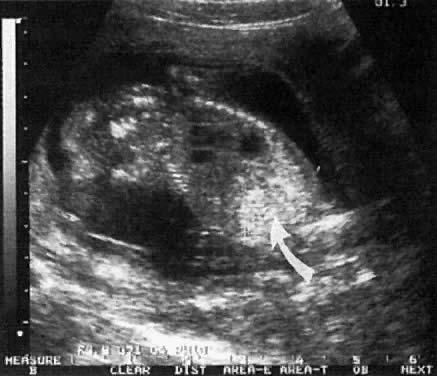

Multicystic-Dysplastic Kidney Disease

The etiology of this condition may be secondary to a chromosomal abnormality or a mutant gene. It is rare, occurring at a rate of 1:10,000 births, and has a male-to-female ratio of 2:1. The condition is unilateral in 75% of cases.

The etiology is related to either (1) poor induction of nephron formation or (2) obstructive uropathy. Defects in nephron formation occur early in embryogenesis, thus impeding renal development. In such cases, the kidneys are very small, each weighing as little as 1 g, and cysts are evident only via microscopic examination. This defect is classified as Potter type II-B dysplastic kidney.55 If the defect develops by 9 to 13 postmenstrual weeks, the fetal kidney assumes a large multicystic appearance (Potter type II-A; Fig. 18).

Fig. 18. Cross-section of fetal abdomen at level of kidneys (spine anterior) shows both kidneys. Note pyelectasis of right kidney (anteroposterior diameter = 6.4 mm). The left kidney is enlarged and uniformly cystic, with no apparent renal cortical tissue, which is characteristic of multicystic kidney.